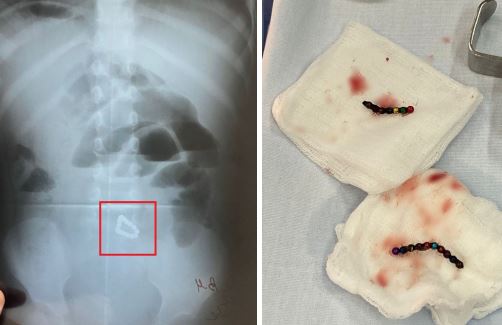

В Уфе медики спасли малышку, проглотившую 17 магнитных шариков